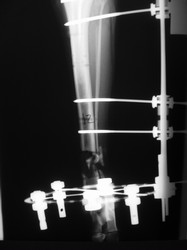

Fijación Externa

PRÁCTICAS CURSO DE FIJACIÓN EXTERNA PERFECCIONAMIENTO.

Híbrido.